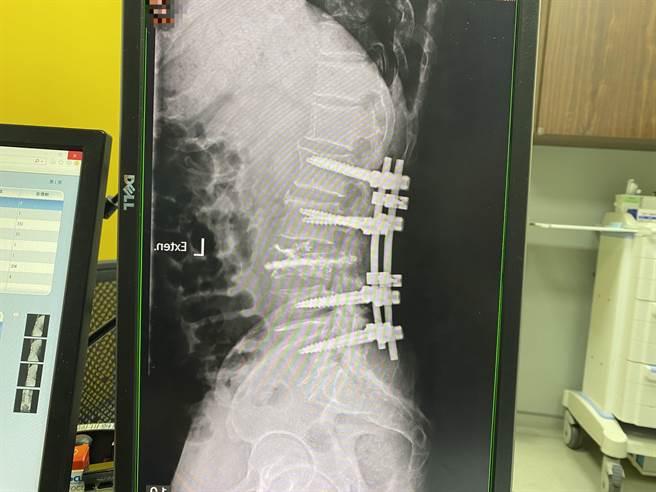

因陳先生的神經已經造成損傷,李漢忠緊急安排手術,進行腰椎椎板切除固定術,椎板切除跟腫瘤切除的目的是做神經減壓跟取得病理報告,皮質骨釘固定的用意是減少因為骨折所造成的脊椎疼痛,手術很順利,在醫護人員照顧下,五天後情況漸改善且康復出院,目前腰痛腳麻減緩很多,也可以站立行走了,後續轉介胸腔科做肺癌治療。

病患進行腰椎椎板切除固定術,目前腰痛腳麻減緩很多,也可以站立行走了。(馮惠宜攝)